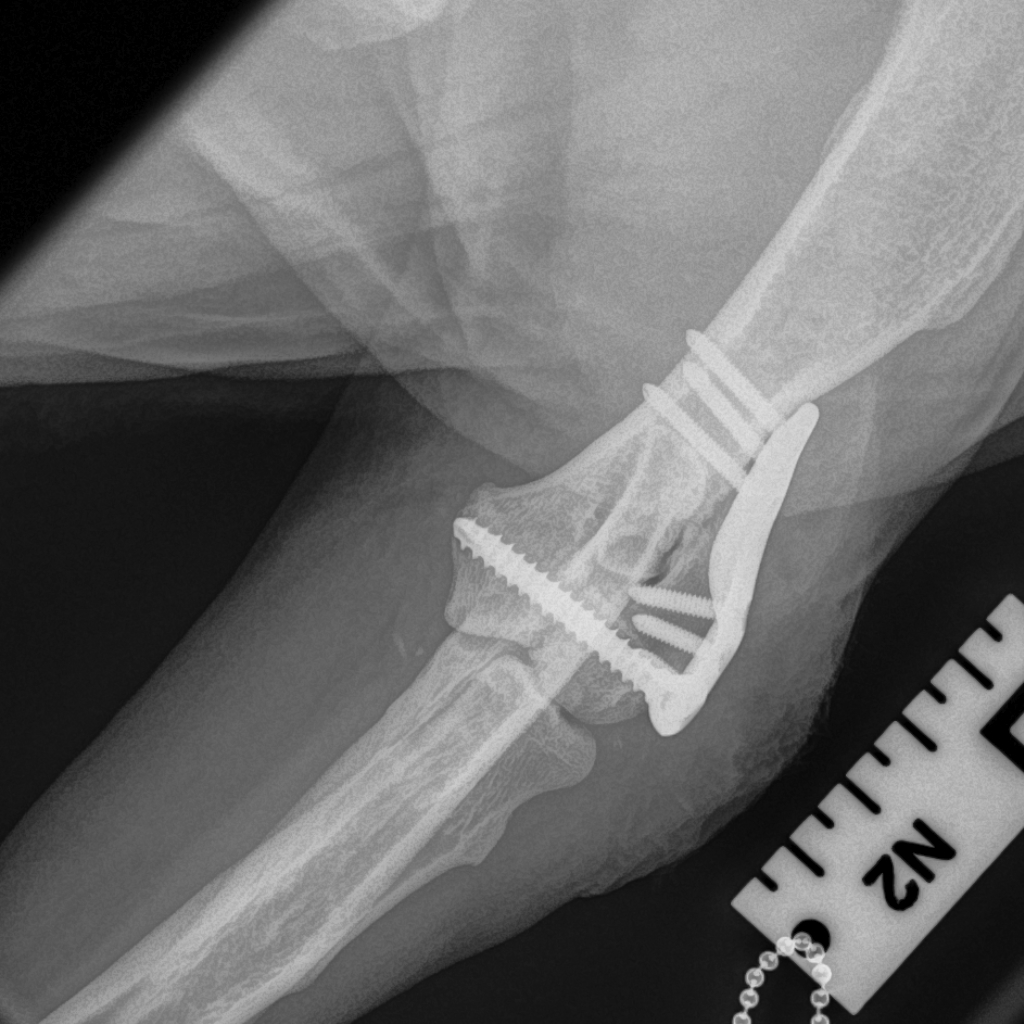

The Lateral Epicondylar Anatomical Plate was developed by Movement’s very own Ben Walton, in collaboration with engineers at Fusion Implants. This locking plate system is designed for the complex anatomy of the lateral epicondyle in breeds of dog such as Springer Spaniels and French Bulldogs.

The plate was designed from CT images from previous patients so that the pre-contouring is a good fit and the screw holes and direction are in the ideal position.

The plate is used in combination with a transcondylar implant such a cortical screw or HIRS implant.